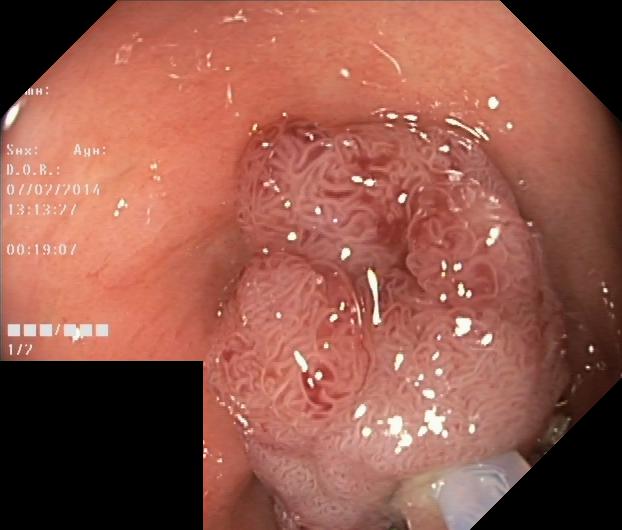

The Kvaris-SEG (Jha et al., 2020c) training dataset can be downloaded from https://datasets.simula.no/kvasir-seg/. It contains 1,000 polyp images and their corresponding ground truth mask as shown in Figure 1. The dataset was collected from real routine clinical examinations at Bærum Hospital in Norway by expert gastroenterologists. The resolution of images varies from to pixels. Some of the images contain a green thumbnail in the lower-left corner of the images showing the scope position marking from the ScopeGuide (Olympus) (see Figure 2). We annotate another separate dataset consisting of 160 new polyp images and use the resulting dataset as the test set to benchmark the participants’ approaches. Figure 2 shows some examples of test images used in the challenge.